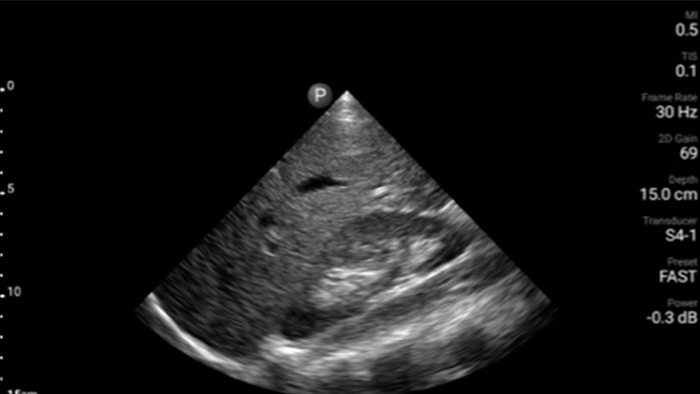

Get the full picture with clear whole-body imagery for a fast, accurate response during an emergency.

• 4 to 1 MHz extended operating frequency range • 2D, color Doppler, M-mode, advanced XRES and multivariate harmonic imaging • High-resolution imaging for abdominal and cardiac applications: Cardiac, OB/GYN, Lung, Abdomen and FAST imaging preset optimizations Lumify aids life-saving technology in prehospital setting

Focused Assessment with Sonography in Trauma (FAST) exam